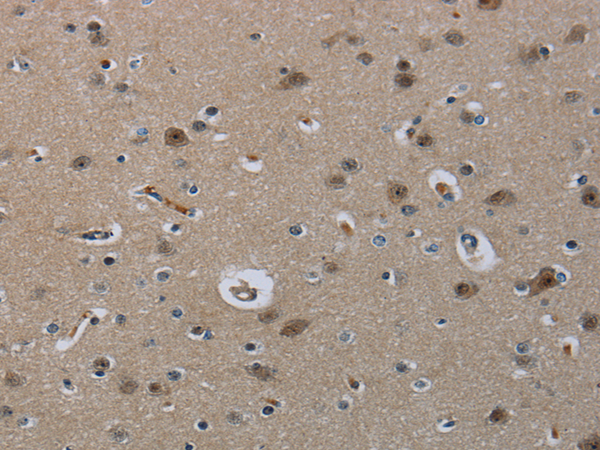

分类: 科研抗体货号: P01509别名: LCMT; PPMT1; CGI-68应用: IHC反应种属: Human, Rat